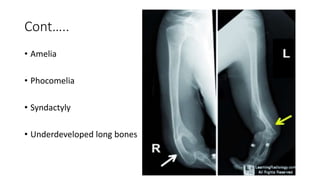

Cont…..

• Amelia

• Phocomelia

• Syndactyly

• Underdeveloped long bones

• #7 White arrow: fusion at the elbow joint and absence of fingers; Yellow arrow: absence of radius and shortening of ulna